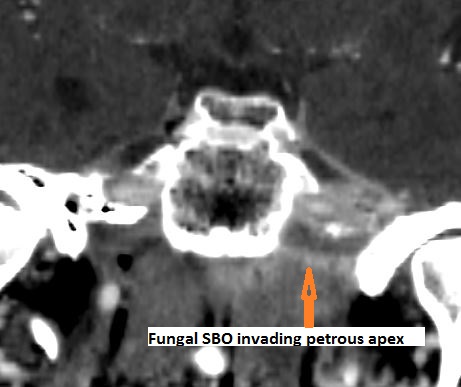

Skull Base Osteomyelitis

Skull base osteomyelitis (SBO) not related to necrotizing otitis externa (NOE) as described above.

Petrous apicitis with an etiology other than associated with middle ear and mastoid disease.